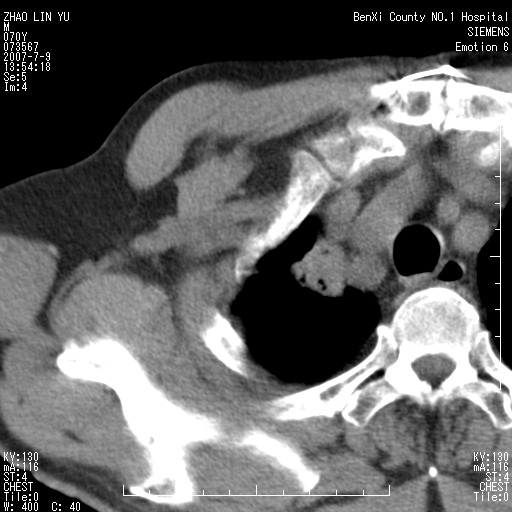

以下是引用王靖旗在2007-7-10 17:12:00的发言:[br] 男、70、咳嗽两个月,半年前换瓣手术,胸片未见异常,于昨天行x片发现右肺上野大片影,行ct扫描,这里是减薄图像,余肺正常。明天晚上会有增强扫描片,到时我会上传。[br][br] 冠状位请大家细看,应该是有意义的,[br][br] 请大家先看平扫发表意见。[br][br]

以下是引用zhangzhongshou在2007-7-10 21:43:00的发言:[br]右肺上叶周围型肺癌,以孤立型细支气管肺泡癌可能性大。